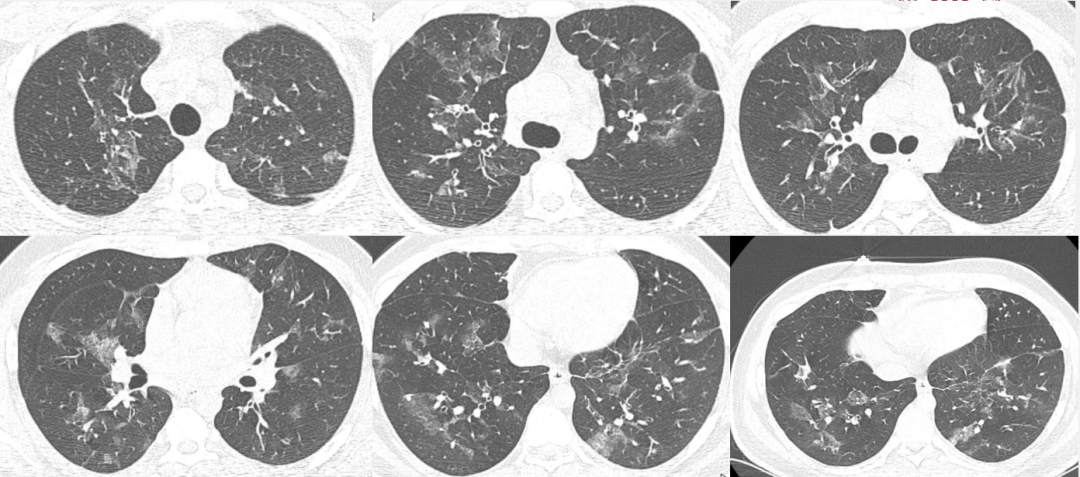

继续抗感染治疗:玛巴洛沙韦+奥司他韦,艾沙康唑+哌拉西林他唑巴坦。但患者氧合指数仍波动于140~180 mmHg。11月3日患者开始出现皮下气肿,胸片较前明显进展(图8),氧合较前恶化。11月5日体温升高(图9),下调PEEP后,氧合基本维持在100 mmHg左右,PaCO2没有升高。血压下降至90/50 mmHg,白细胞较入院时没有明显升高,CRP从正常升至22.7 mg/ml,PCT正常。气管镜下分泌物较前增多,黄色黏稠状,培养结果未出。

图片

图8  患者胸部X线片(2023年11月3日)

由于患者出现了气压伤,因此加大了镇痛镇静力度,并且予适当的肌松剂,考虑患者痰液排出困难,进行了气管切开,加强痰液引流。患者氧合有所改善,维持在100~200 mmHg,PaCO维持在50 mmHg以内,分钟通气量为6~7 L/min,仍有发热(图10)。11月11日(气管切开后,PEEP下调)胸部X线片可见皮下气肿和气压伤好转,但肺容积较前减少(图11)

图11  患者11月11日胸片

2023年11月20日胸部CT显示窦道形成,2024年1月14日胸部CT可见恢复较好,病变基本吸收(图13)

图13  患者胸部CT